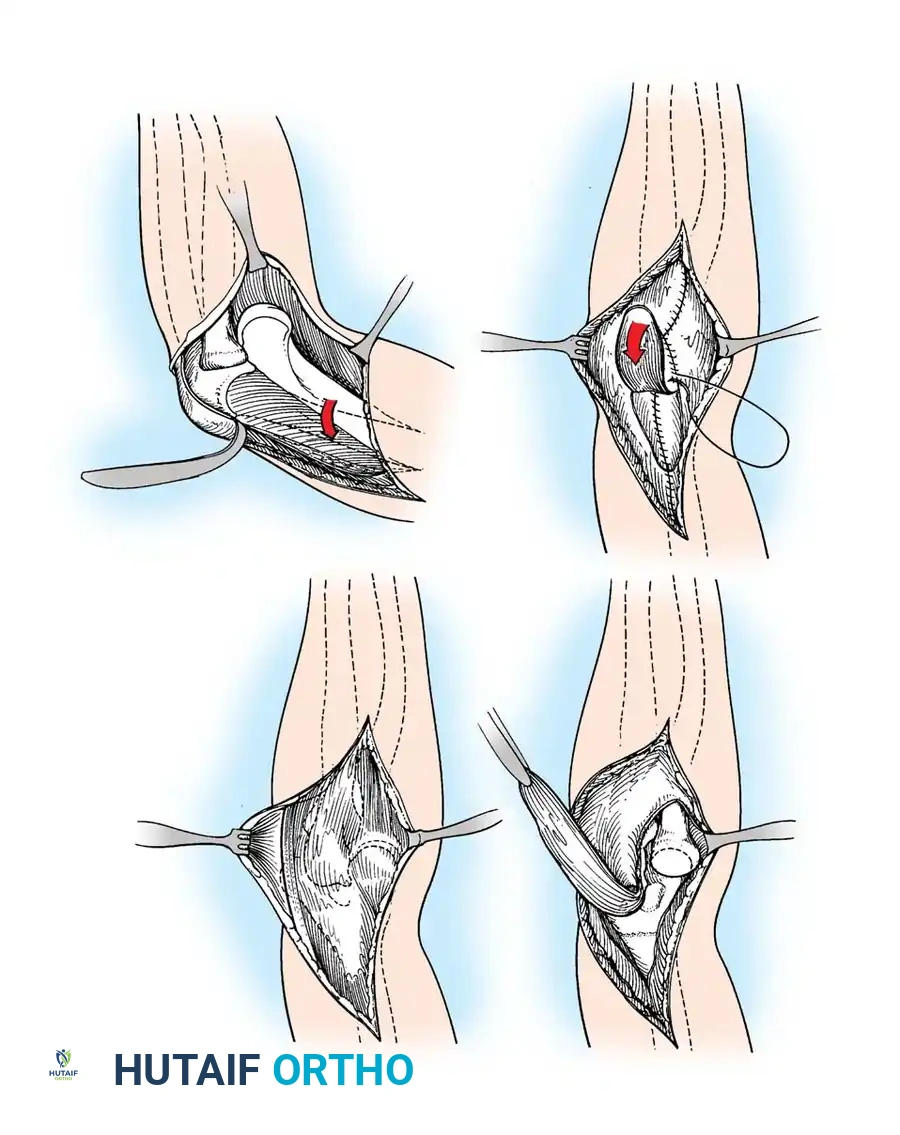

Triceps Flap and Subperiosteal Stripping

Beginning proximally, use sharp dissection to reflect the aponeurosis of the triceps distally, forming a robust tongue-like flap of tissue that remains attached to the olecranon.

Starting 7.5 cm proximal to the joint, make a midline incision through the underlying muscle fibers of the triceps down to the olecranon. Curve this deep incision around the lateral edge of the olecranon.

Fig. 58-26 Speed technique of open reduction. A, Incision and ulnar nerve isolation. B, Triceps aponeurosis reflected distally; subperiosteal stripping of muscles. C, Lateral view showing extent of mobilization. D, V-Y closure.

Subperiosteally free all muscle attachments from the distal humerus, both anteriorly and posteriorly.

Aggressive subperiosteal elevation is required to mobilize the distal humerus completely.

Release the attachments of the joint capsule and collateral ligaments around the humeral condyles. Mobilizing the tissues around the medial condyle and anterior humerus can be exceptionally difficult due to scarring, but complete mobilization of the distal humerus is non-negotiable for reduction.

Joint Debridement and Reduction

Extensive callus and heterotopic ossification are typically found on the posterior humerus and within the olecranon fossa.

Use a rongeur and high-speed burr to meticulously clear the olecranon and coronoid fossae of all fibrous tissue and callus.

Once the distal humerus is free, expose the radial head and clear the trochlear notch of the ulna. To reduce the joint, apply gentle traction, rotate the forearm, and press on the anterior surface of the capitellum to lever the radial head anteriorly into position. If resistance is met, do not use excessive force; instead, widen the soft-tissue release to prevent iatrogenic cartilage damage. Once the radial head is reduced, slip the coronoid process distally and anteriorly over the trochlea.

Stabilization and Closure

Carry the joint through a full range of motion. Because the collateral ligaments have been released, the elbow is frequently grossly unstable.

If highly unstable, transfix the olecranon to the humerus with one or two smooth Steinmann pins with the elbow at 90 degrees of flexion.

Suture the periosteum and deep triceps fibers over the posterior humerus. Advance the V-Y tongue of the triceps aponeurosis and suture it into its normal position, or slightly more distally to accommodate the lengthened state. Decompress the wound with a closed suction drain and close the skin in layers.